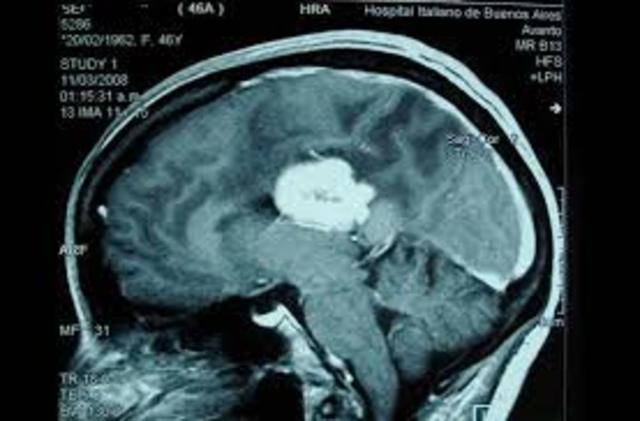

2.Tumores

se define como una reducción, o ausencia completa de la irrigación sanguínea puede ser: Isquemia Global: , cuando el flujo sanguíneo es insuficiente para cubrir las demandas metabólicas del cerebro, causado por un paro cardíaco, una isquemia prolongada conduce al infarto. Isquemia Focal:se produce cuando un coágulo de sangre ha ocluido un vaso cerebral lo que reduce el flujo de sangre a una región específica aumentando el riesgo de muerte celular, causada por trombosis o embolia